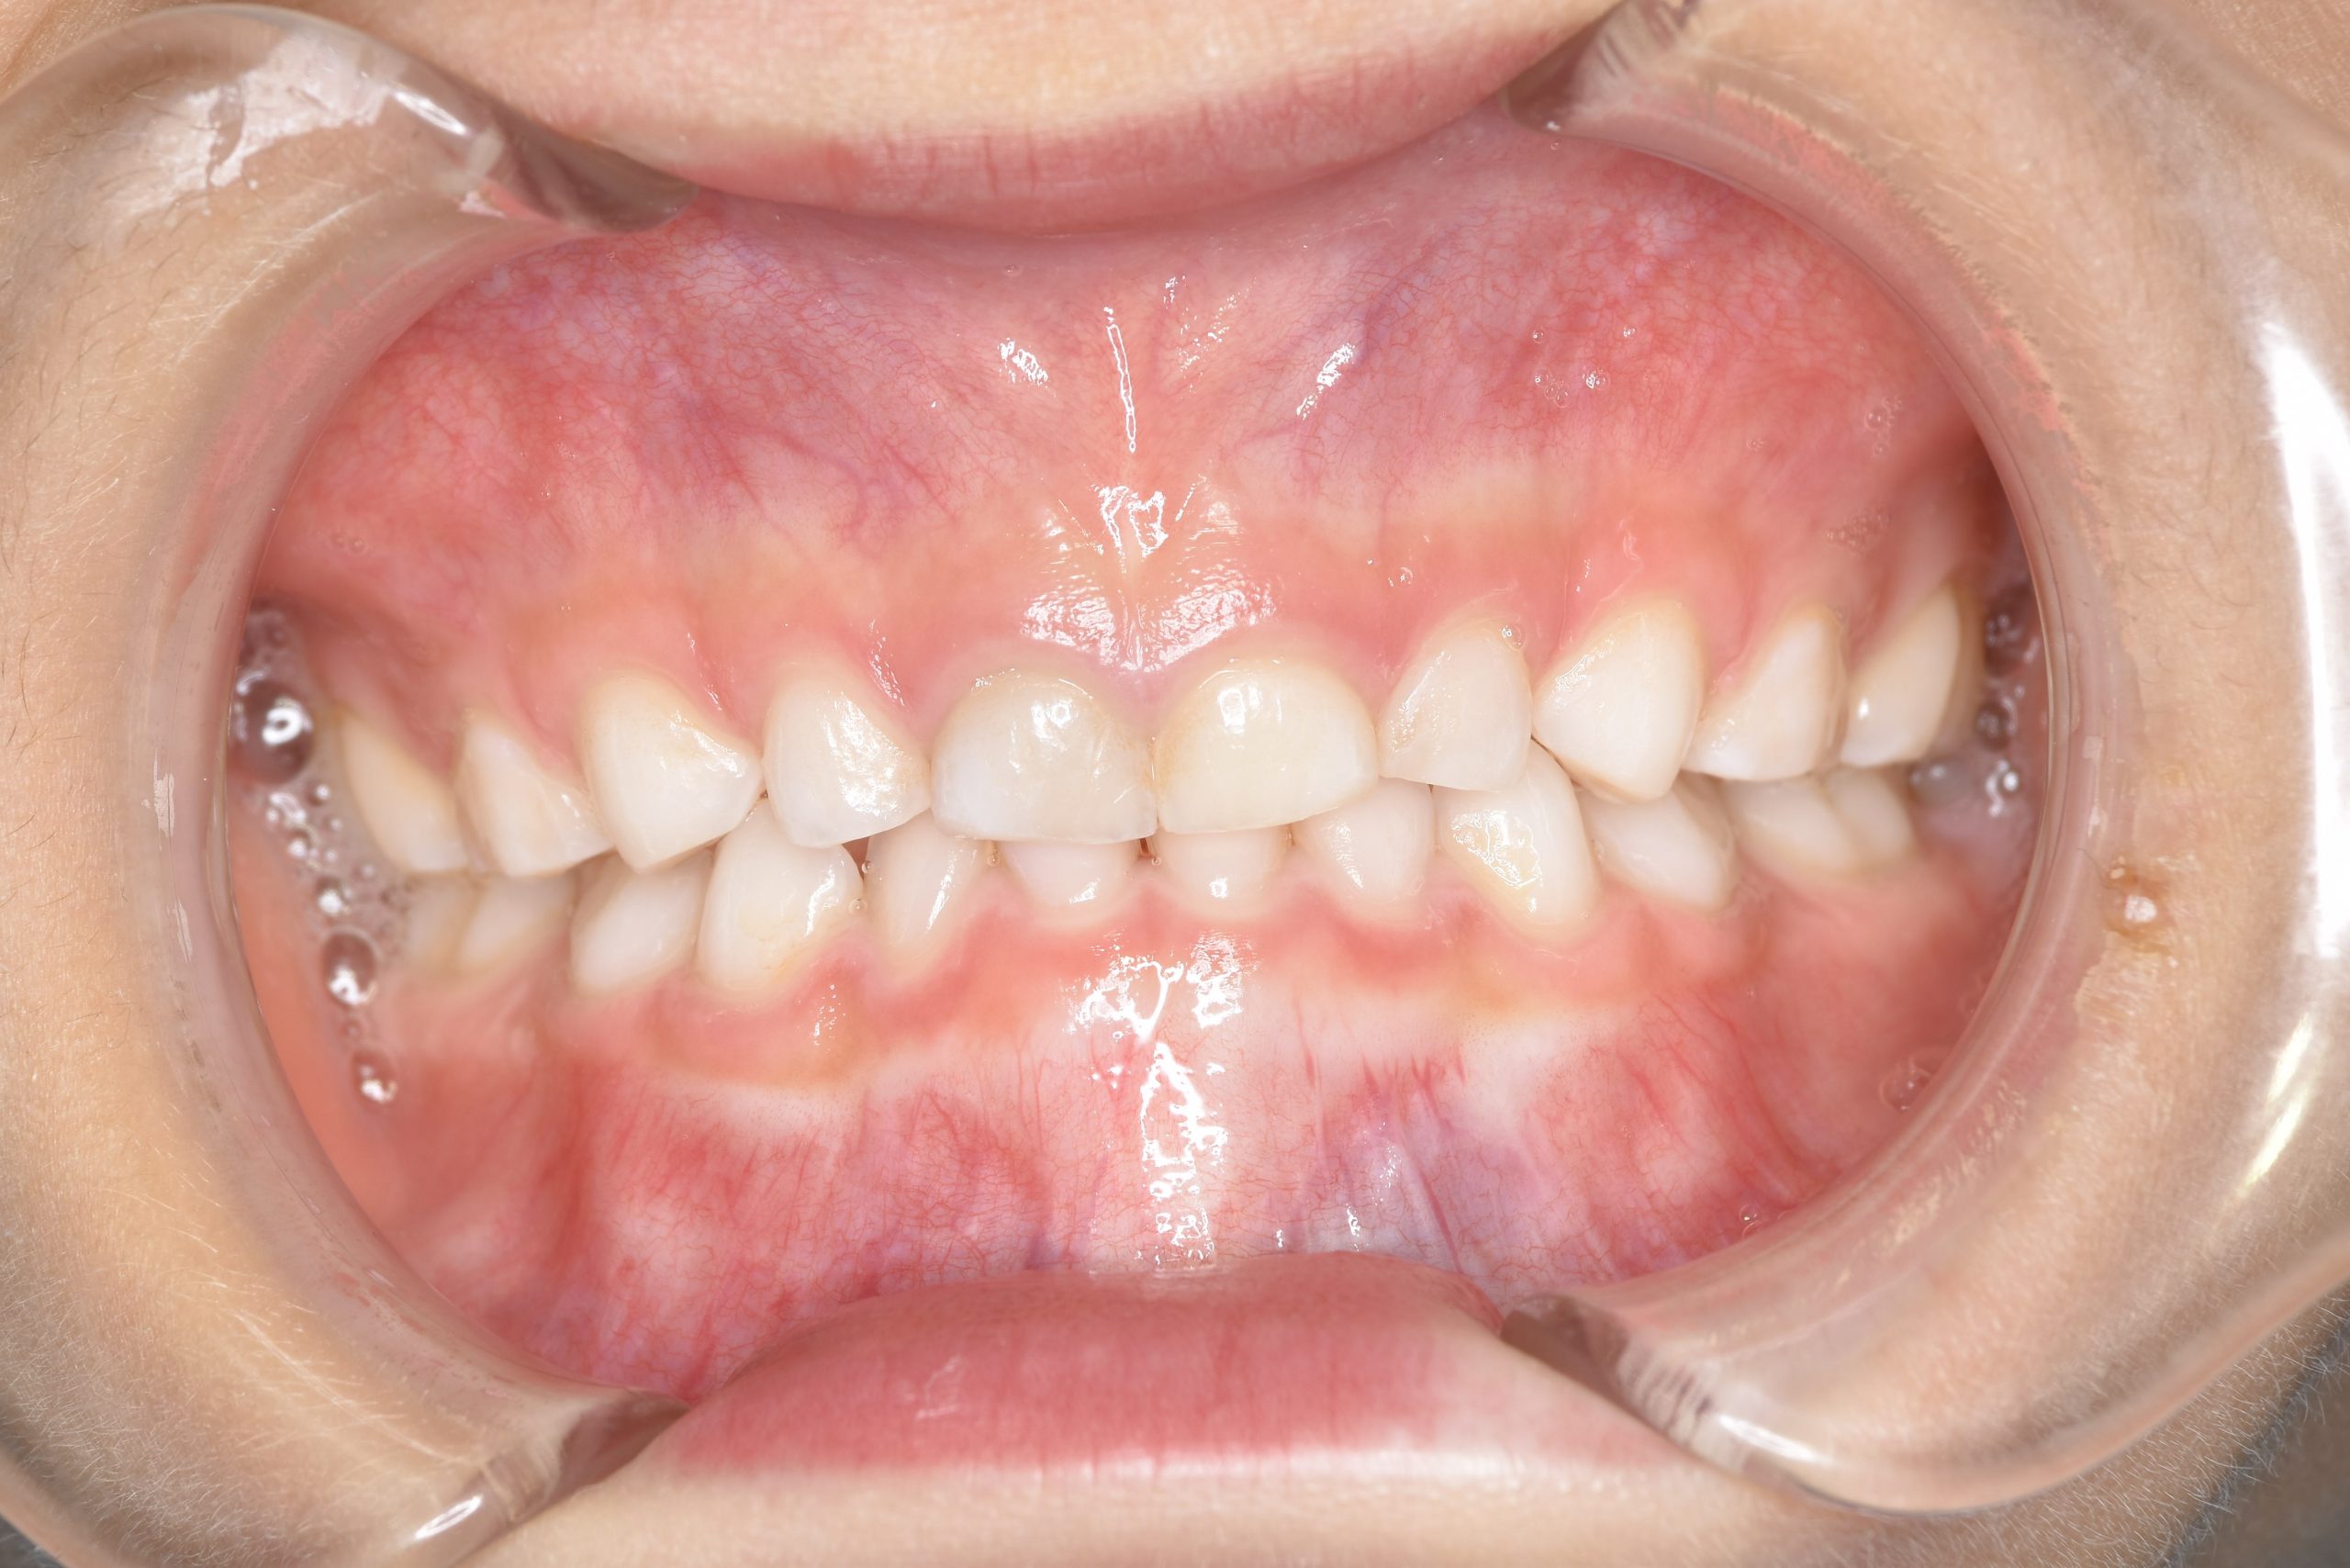

ビフォー

子どもの矯正治療|症例_121

主訴 歯並び

施術内容 上顎急速拡大装置と下顎リンガルアーチを用いて上下顎骨を拡大した。

その後マウスピース型矯正装置で歯牙を配列し良好な咬合を獲得した。

治癒期間 3年11ヶ月間